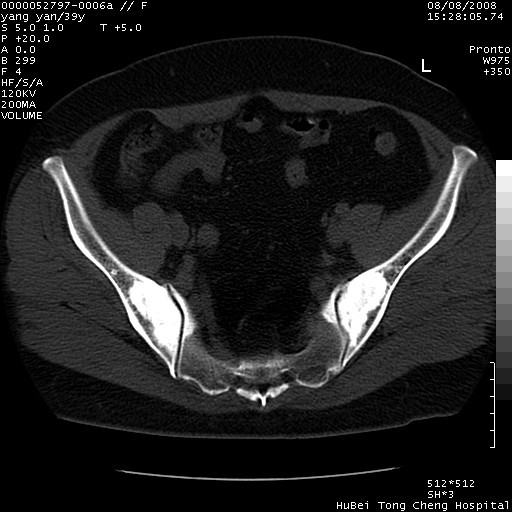

患者 女,39岁。因外伤检查,偶然发现。

典型!双侧骶髂关节致密性骨炎。

病变累及髂骨关节面,腰椎椎小关节结构紊乱,不除外强直性脊柱炎,建议结合实验室检查

典型!病变主要累及双侧髂骨。常见于育龄期妇女。

髂骨致密性骨炎系一种以骨质硬化为特点的非特异性炎症,有高度致密的骨硬化现象,尤其以髂骨下2/3更为明显,但关节间隙则无改变。因位于骶髂关节,且该关节症状明显,故又称之为“骶髂关节致密性骨炎”。 本病90%以上为中年女性,以妊娠后期、尤其分娩后为多见,亦可见于尿路或女性附件慢性感染后,或盆腔内其他感染。此外,臀骶部的外伤亦可诱发或引起本病。  妊娠、分娩及外伤均可引起骶髂关节韧带的撕裂而易使局部的血供受阻。因此早期局部呈现充血、水肿及渗出增加等,渐而局部出现增生与变性反应,随着胶原纤维的致密化而向硬化演变;血管形成厚壁血管,易闭塞而引起髂骨耳状面处缺血和缺氧,骨质呈现硬化性改变,以致手术时局部出血较少。骶髂关节囊壁显示纤维增生、弹性降低及松动样改变。继发于盆腔内炎症者亦出现相类似的病理改变,可能系细菌内毒素作用所致。